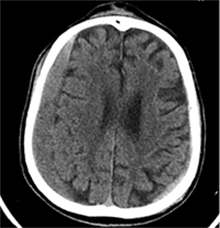

Praėjus dar 2 sav., pacientas iš slaugos ligoninės atvežtas dėl vangumo, dezorientacijos, nerišlios ir sulėtėjusios kalbos. Atlikus GKT, dešinėje pusėje po kraniotomijos lopu įtarta poūmė (ūmi) epidurinė hematoma, nesant VSD. Per parą pacientas operuotas. Operacijos metu po minkštaisiais audiniais rasta kraujo sankaupa su seroziniu komponentu, paimtas bakteriologinis pasėlis. Po KPL rasta krešulių su skystu krauju ir seroziniu komponentu. Paimtas antras bakteriologinis pasėlis, įtariant infekciją. Hematoma (seroma) pašalinta. Žaizda plauta mažos koncentracijos betadinu ir fiziologiniu tirpalu. Kraujavimo iš KSD nepastebėta. Nuspręsta KPL grąžinti – labiau tikėtina epidurinės seromos (EDS) diagnozė. Siekta uždaryti „negyvąjį“ epidurinį tarpą, pakabinant KSD centre prie KPL siūlais, tačiau KSD buvo nepaslankus, tampriai priaugęs prie smegenų. Atlikus kontrolinę GKT (9 pav.), nustatyta teigiamų pooperacinių pakitimų, smarkiai sustorėjęs KSD, tarpas tarp KPL ir KSD. VSD nenustatyta. Po operacijos paciento bendroji būklė buvo stabili. Reakcija buvo kiek sulėtėjusi, tačiau vyras gebėjo atsakyti į elementarius klausimus. Teigiama klinikinė dinamika. Po savaitės pacientas tapo labai vangus, sulėtėjo, skundėsi silpnumu, kalbėjo nesklandžiai. Pakartojus GKT (10 pav.), nustatyta padidėjusi epidurinė skysčio sankaupa, panaši į mišraus tankio hematomą (apie 64 ml tūrio) dešinėje pusėje frontotemporoparietaliai, padidėjusi VSD į kairę – iki 4 mm. Kadangi pacientas per tą patį randą jau operuotas 6 kartus, o po operacijų pastebimos vis atsinaujinančios pakartotinės EDS, priimtas sprendimas neskirti operacinio gydymo. KPL turėjo daugybinių perforacijų, todėl nuspręsta atlikti subgalinio tarpo punkciją, tikintis, kad per perforacijas išbėgs EDS. Atlikus punkciją, gauta 20 ml serohemoraginio skysčio. Po procedūros paciento būklė pagerėjo, jis tapo kiek aktyvesnis, tačiau efektas nebuvo patenkinamas. Kitą dieną nuspręsta punktuoti pakartotinai, gauta 4 ml serohemoraginio skysčio. Tūris buvo nepakankamas teigiamam efektui gauti. Priimtas sprendimas skirti lašinių infuzijų ir švelnią osmoterapiją neurologinei simptomatikai sumažinti. Punkcijos nedavė norimo efekto, todėl nuspręsta suformuoti poodinę neigiamo slėgio drenažinę sistemą po minkštųjų audinių lopu. Į subgalinį tarpą įvestas 20G periferinės venos kateteris, fiksuotas prie odos ir sujungtas su uždara vakuumine sistema, tikintis nuolatinio drenavimosi smegenų kompresijai sumažinti. Per 5 lovadienius išsiskyrė apie 50 ml serohemoraginio skysčio. Atlikus kontrolinę GKT, buvo matyti teigiama dinamika (11 pav.). Dėl infekcijos profilaktikos vakuuminė sistema pakeista 2 kartus. Įvedus vakuuminę sistemą, po 12 lovadienių paciento būklė pagerėjo, jis tapo aktyvesnis, į klausimus atsakydavo prasmingai, paliepimus vykdydavo visomis galūnėmis. Vakuuminė sistema pašalinta. Po 2 dienų atlikta GKT (12 pav.). EDS dešinėje pusėje regresavo, smegenų kompresijos nenustatyta. Esant stabiliai būklei ir teigiamai dinamikai, pacientas grąžintas į slaugos ligoninę.

12 pav. Dešinė F-T-P EDS dinamikoje sumažėjusi (VSD nematyti)